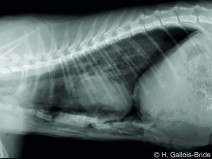

• Plan modulaire en scanner intermédiaire 1 : Thorax et abdomen (Dardilly)

Principes du plan modulaire

Le plan de formation est composé de 3 modules organisés par niveau.

Ces trois modules peuvent être réalisés à la suite les uns des autres mais ne peuvent pas être suivis dans le désordre. Les notions y seront en effet abordées selon un fil conducteur précis qui vise à permettre une progression dans la...